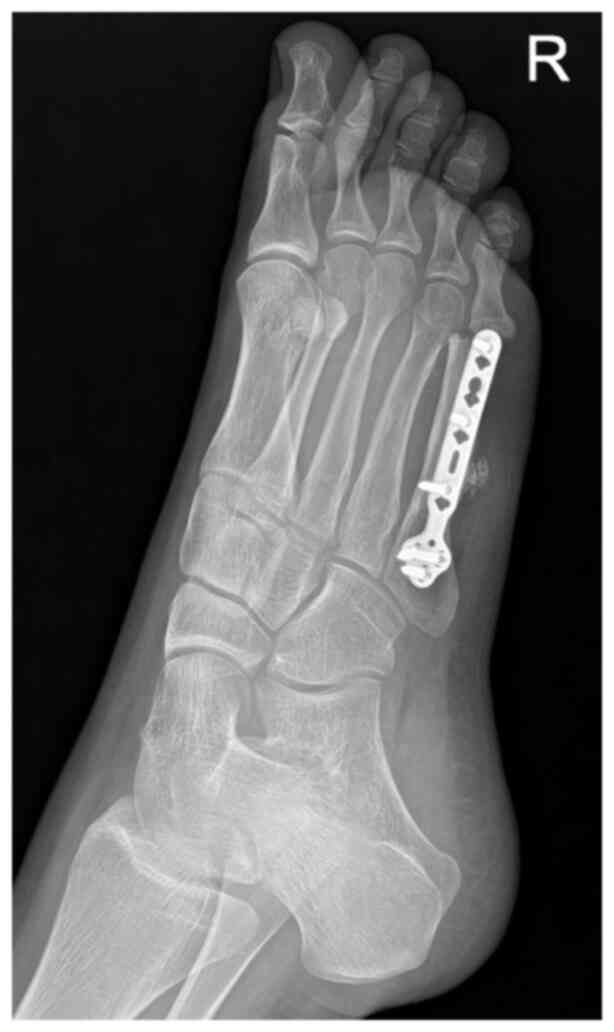

In January 2019, an 11-year-old female was referred to the Masaryk Memorial Cancer Institute Sarcoma Center with a 2-month history of pain in the right foot. MRI scans showed a 3 cm thickening of the bone in the V. metatarsal diaphysis (Fig. 11). The histopathology report showed an intermediate-grade periosteal osteosarcoma (Fig. 12). The patient had no lymph node involvement or metastases. The Musculoskeletal Tumor Committee recommended en bloc resection with bone allograft reconstruction using a plate. The final histopathology report confirmed the initial findings from the biopsy (Fig. 13). After 2 years, a follow-up plain radiographs showed ossification on the allograft surface (Fig. 14), leading to a biopsy to check for any signs of local recurrence. The biopsy results showed no evidence of malignancy (Fig. 15). At the time of writing, the patient completed 5 years of follow-up appointments with no signs of disease recurrence.

Case 3. (A) MRI showing a periosteal osteosarcoma of the fifth metatarsal. (B) Postoperative radiographic imaging following complete resection and reconstruction with a bone allograft and plate fixation.

Case 3. Follow-up radiographic imaging showing suspected ossification on the allograft surface, which prompted a biopsy.